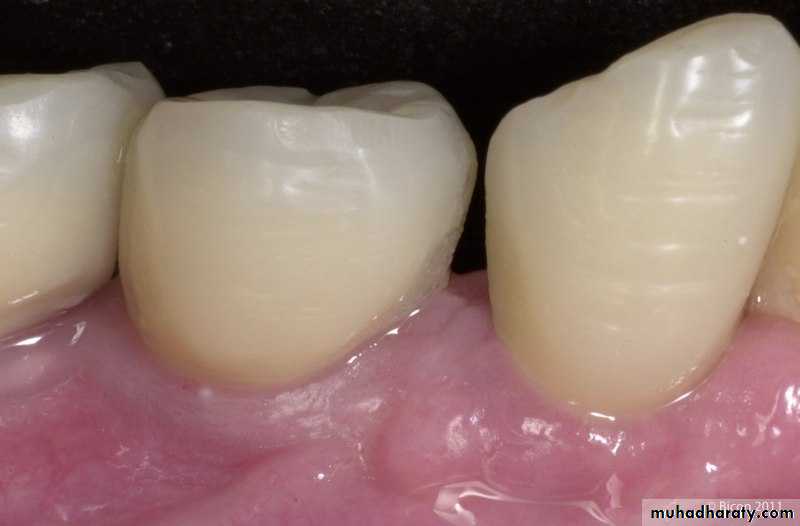

7. Contouring And Finishing Problems

Causes of contouring or finishing problems include:1. Injuring adjacent unprepared tooth structure.

2. Overcontouring the restoration.

3. Undercontouring the restoration.

4. Creating inadequate anatomic tooth form.

Potential solutions include:

1. Be careful with use of rotary instruments.2. Have a proper matrix with appropriate axial and line angle contours.

3. Create embrasures to match the adjacent tooth embrasure form.

4. Use a properly shaped contouring instrument for the area being contoured.

5. Remember the outline form of the preparation.

6. View the restoration from all angles as it is contoured.